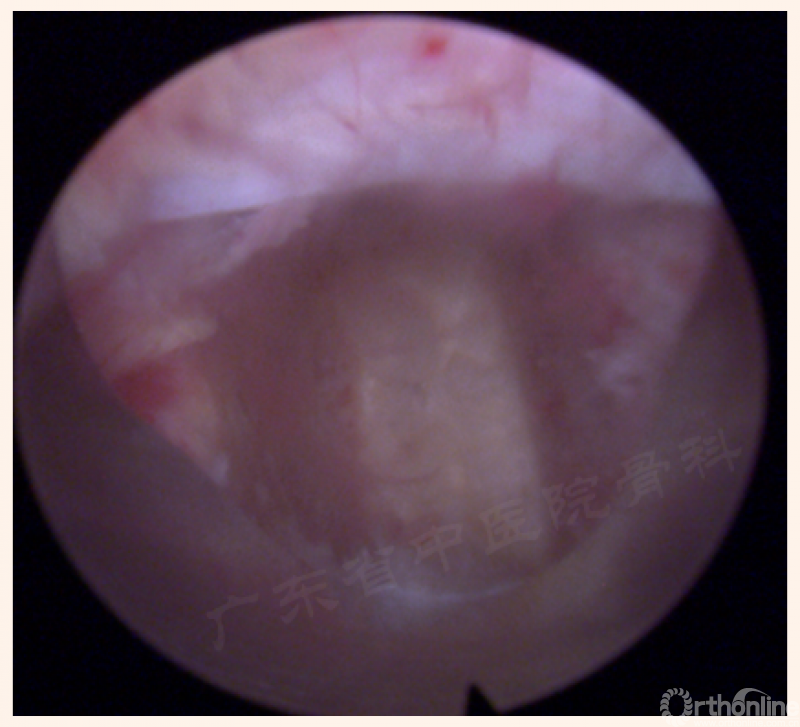

1. 椎间盘显露及开口

(21、22、23、24动图待完善)

2. 后缘处理—颈椎?

3. 进入间隙

关键点-空间